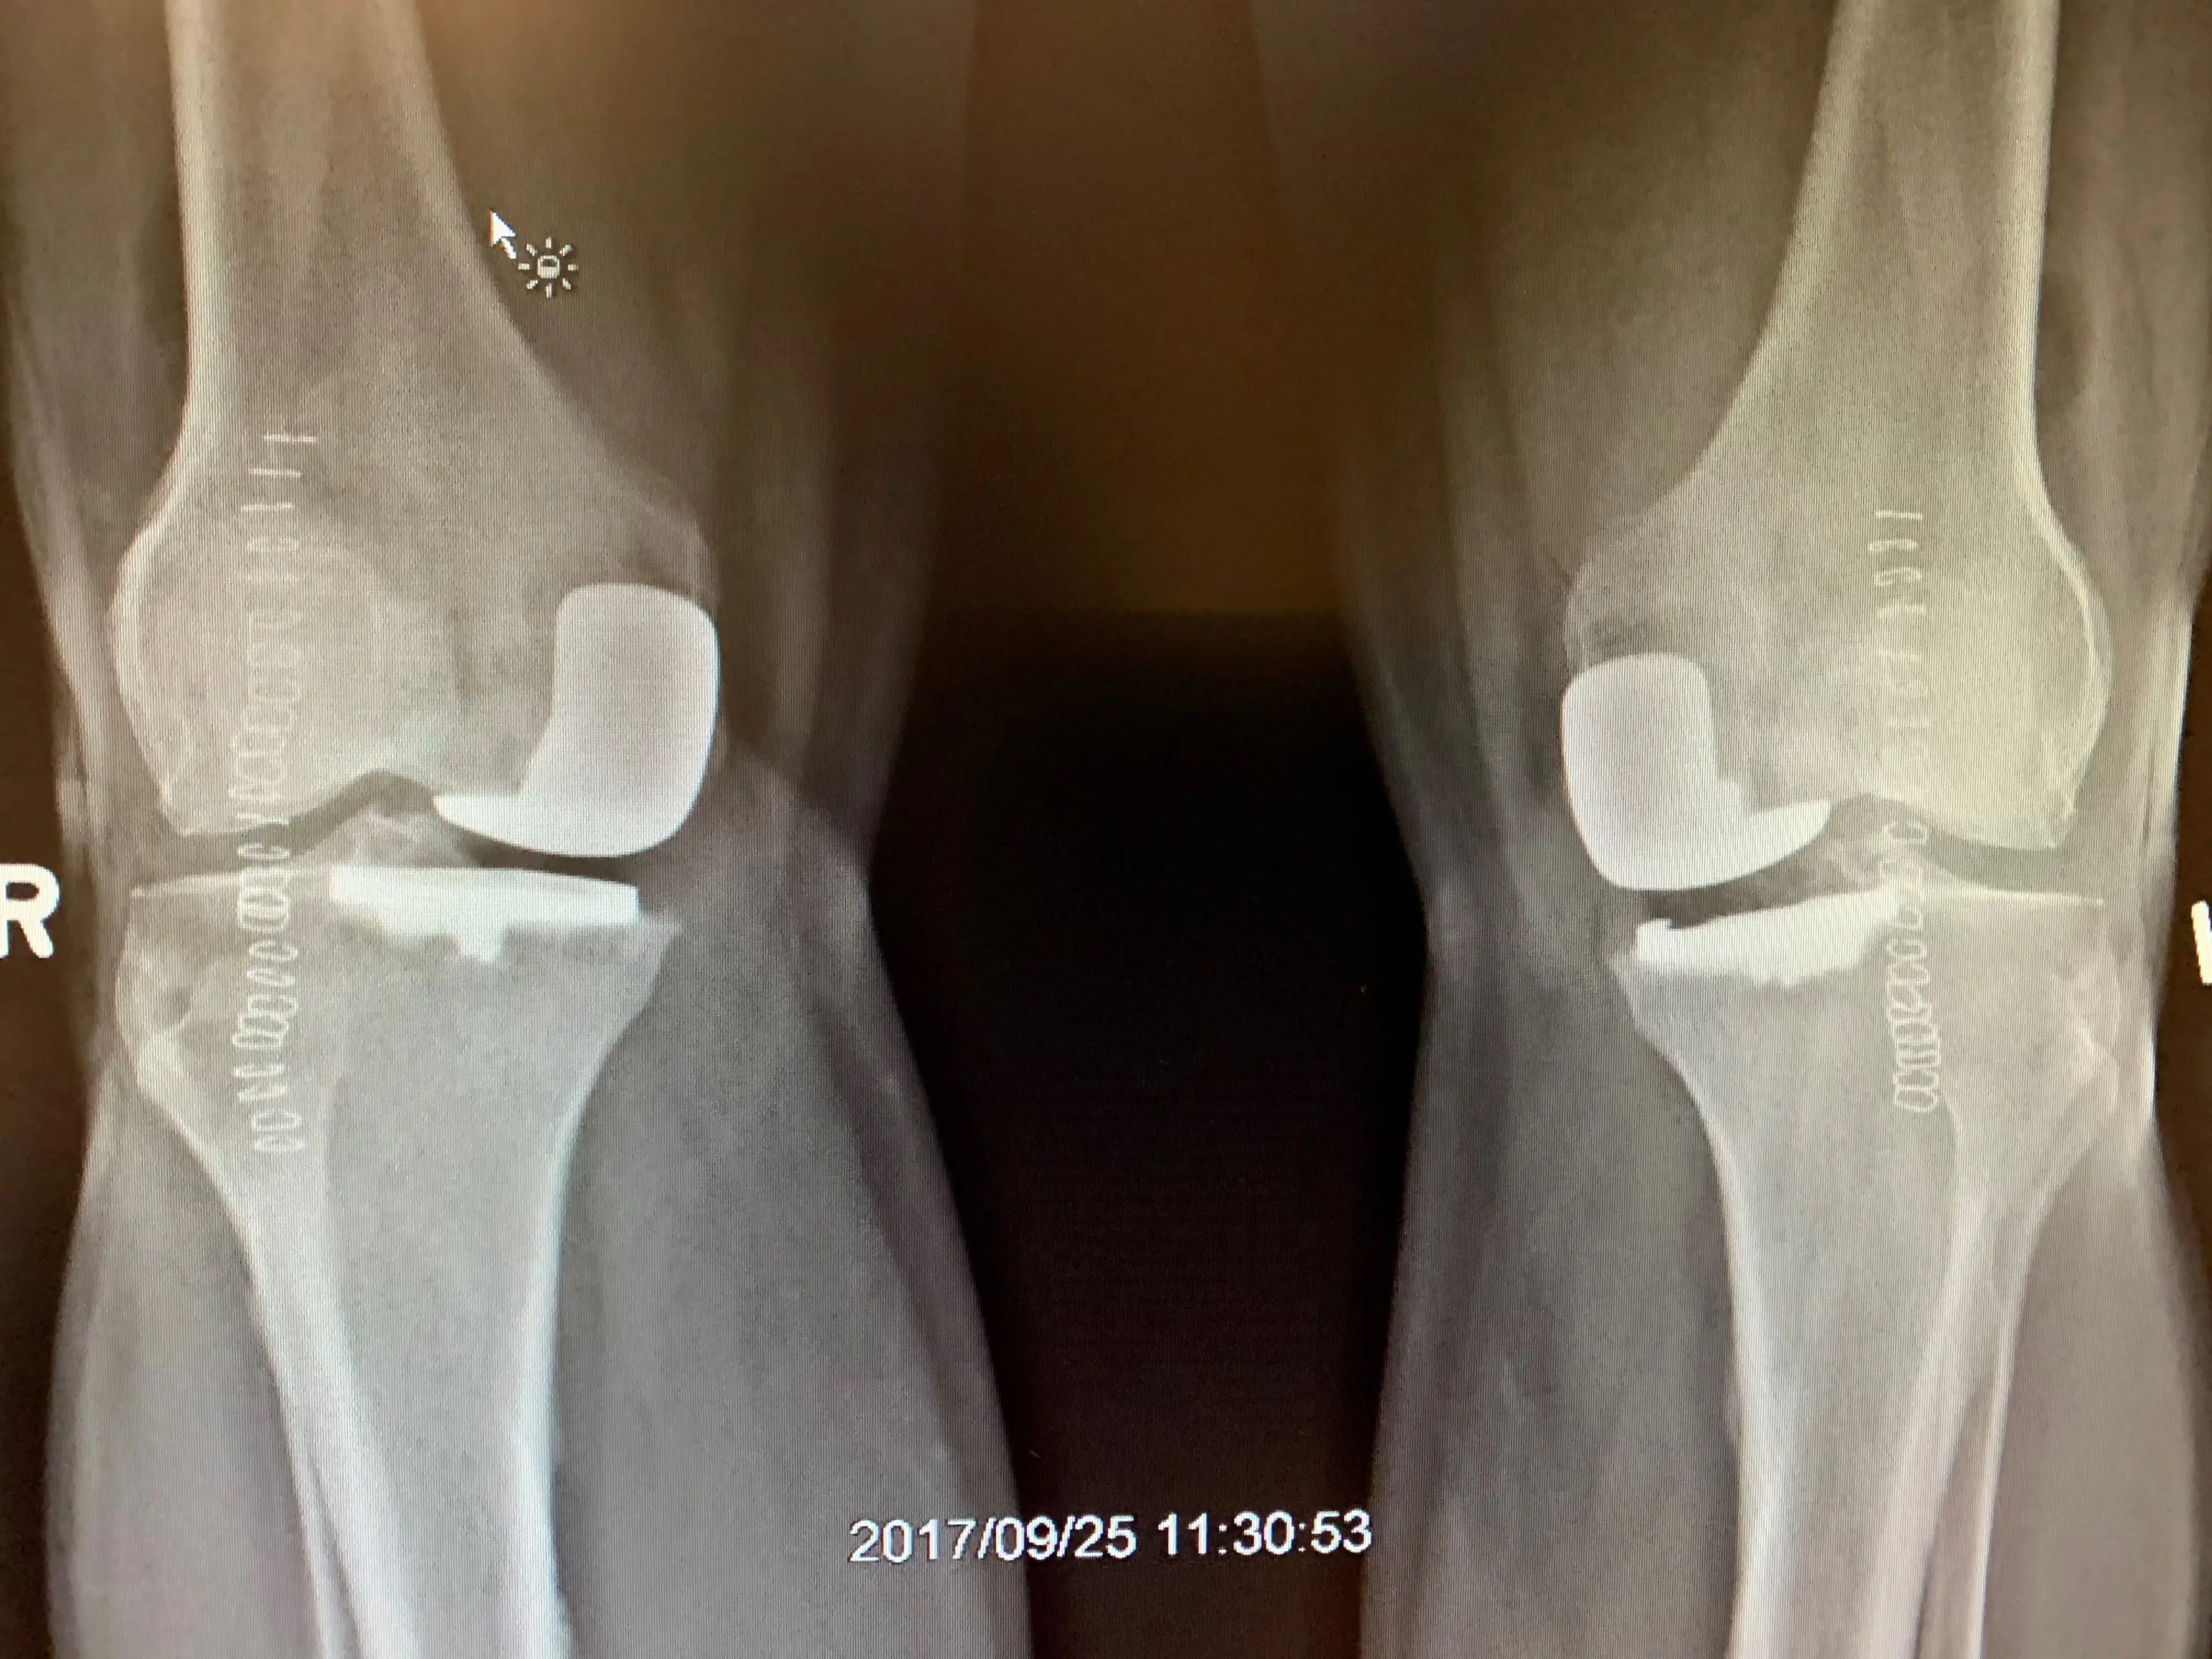

Pre-opSimultaneous bilateral Unicondylar Knee replacement in 67 year old malea

Simultaneous bilateral Unicondylar knee replacement in a 67-year-old male.

Post-opSimultaneous bilateral Unicondylar Knee replacement in 67 year old maleb